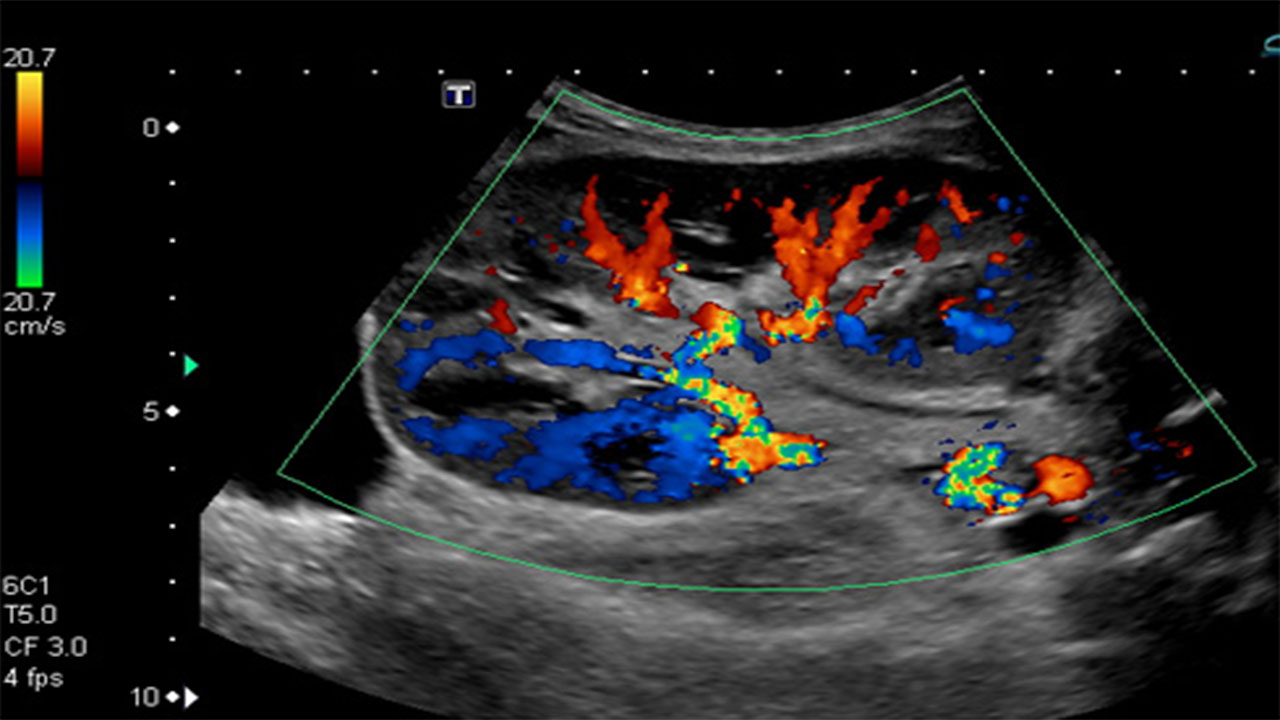

Color Doppler is a medical imaging technique that is used to visualize the movement of blood within the body's blood vessels.

Renal transplant Doppler is a non-invasive ultrasound technique to assess blood flow in the transplanted kidney in post-operative monitoring.

Portal Doppler: Evaluates blood flow in the portal vein of the liver. Renal Doppler: Assesses blood flow in the renal arteries and kidneys.